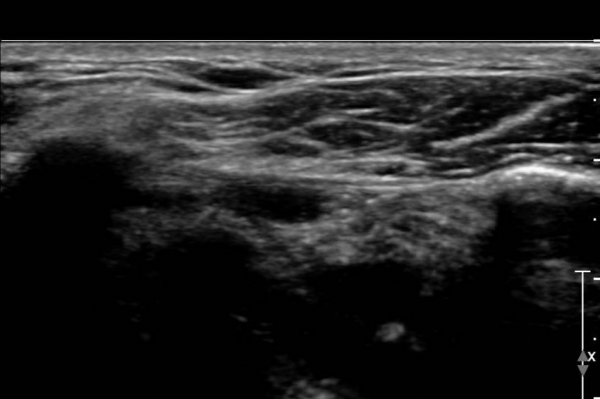

±Ø»ó°Ç Á¾´Ü¸é°Ë»ç»ó ±Ø»ó°Ç ¾Õ(»çÁø 4), Áß°£(»çÁø 5), ÈĹæ(»çÁø 7)¿¡ ±¤¹üÀ§ÇÏ°Ô ¼®È¸¸¦ º¸À̰í

Ⱦ´Ü¸é°Ë»ç(»çÁø 6)¿¡¼­µµ ±Ø»ó°Ç ³»ÃøºÎÅÍ ¿ÜÃø±îÁö ±¤¹üÀ§ÇÑ ¼®È¸°¡ °üÂûµÈ´Ù.